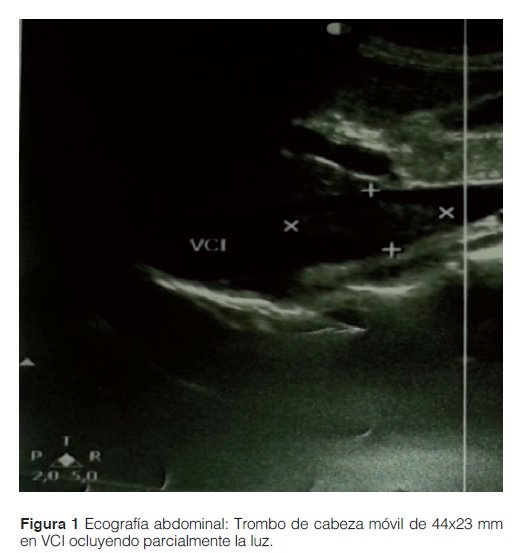

Se realizó una ecografía doppler donde se constató un trombo en la vena cava inferior flotante de 44 x 23 mm por encima de los vasos renales con oclusión parcial del ostium de la vena renal derecha. En la ecografía doppler de miembros no se objetivó datos de valor. En vista a estos resultados se decidió la anticoagulación con heparina de bajo peso molecular.